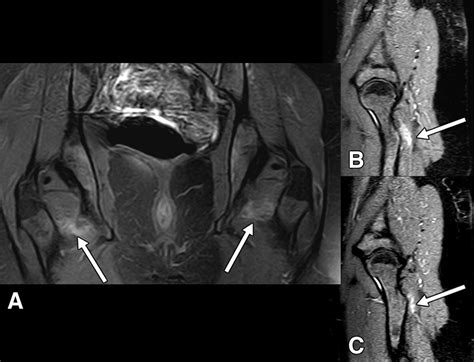

When the Obturator Externus Muscle becomes tight, weak, or injured, it can lead to a variety of symptoms, most notably deep hip pain, referred pain in the gluteal region, or a feeling of “clicking” or “popping” within the hip joint. Because of its deep location, identifying it as the source of pain can be challenging for those unfamiliar with deep pelvic anatomy.

⚠️ Note: If you experience persistent, sharp, or radiating hip pain that restricts your mobility, please consult a medical professional or a qualified physical therapist. Imaging or professional palpation may be necessary to distinguish between muscle strain and hip joint pathologies like labral tears.